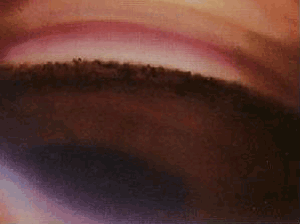

色素分级——色素IV级